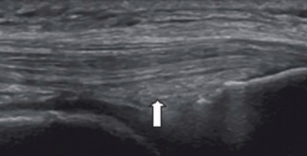

Nerve appearance on US

Nerve fiber enclosed by hyperechoic epineurium

LAX

“Railroad” or “tram track”

Hypoechoic nerve fibers divided by hyperechoic perineurium

SAX

“Honeycomb” pattern

Hypoechoic nerve fibers surrounded by hyperechoic perineurium